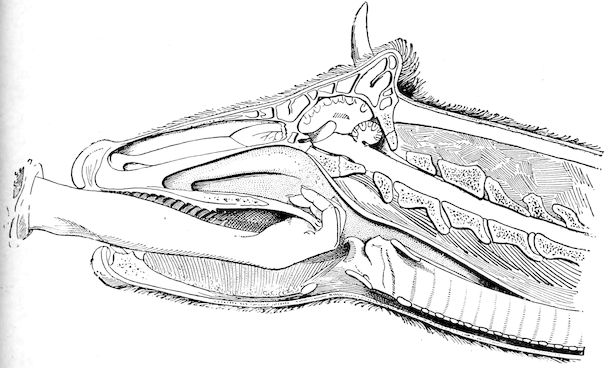

Fig. 9.—C, horn; P, modified skin forming the keratogenous membrane; O, horn core, exhibiting a double sinus.

(2.) The horn-secreting membrane is formed by the skin, which undergoes special development around the base of the horn and comes to resemble that of the coronary band, from which the hoof or claw is secreted. The band is about one-fifth of an inch in breadth. The papillæ of the dermis are specially developed at this point, and the epithelium which they secrete eventually forms the horn.

The internal surface of the growing horn is adherent to the horn core through the medium of another tissue formed by a specially differentiated periosteum which is continuous with the periosteum covering the frontal bone. It is not a true periosteum, but a vascular tissue formed of papillary layers analogous to those of the podophyllous tissue of the ox’s claw or horse’s hoof.

This keratogenous membrane receives a rich vascular supply from the arterial circle formed at the base of the horn core by a division of the external carotid, the blood conveyed by which is freely distributed to the enlarged papillæ. The great vascularity of these parts 23explains why lesions of the horns are often followed by such profuse bleeding.

(3.) The horn secreted by the papillæ of the horn band (which is analogous to that of the coronary band of the horse) forms a cone varying in its curve in various breeds. Its base is hollow, and contains little depressions holding the papillæ from which the horn is secreted. From its base up to the end of the horn core the walls progressively increase in thickness. From this point it is solid; in a fully-grown horn the bone does not extend more than one-half or two-thirds of the entire length.